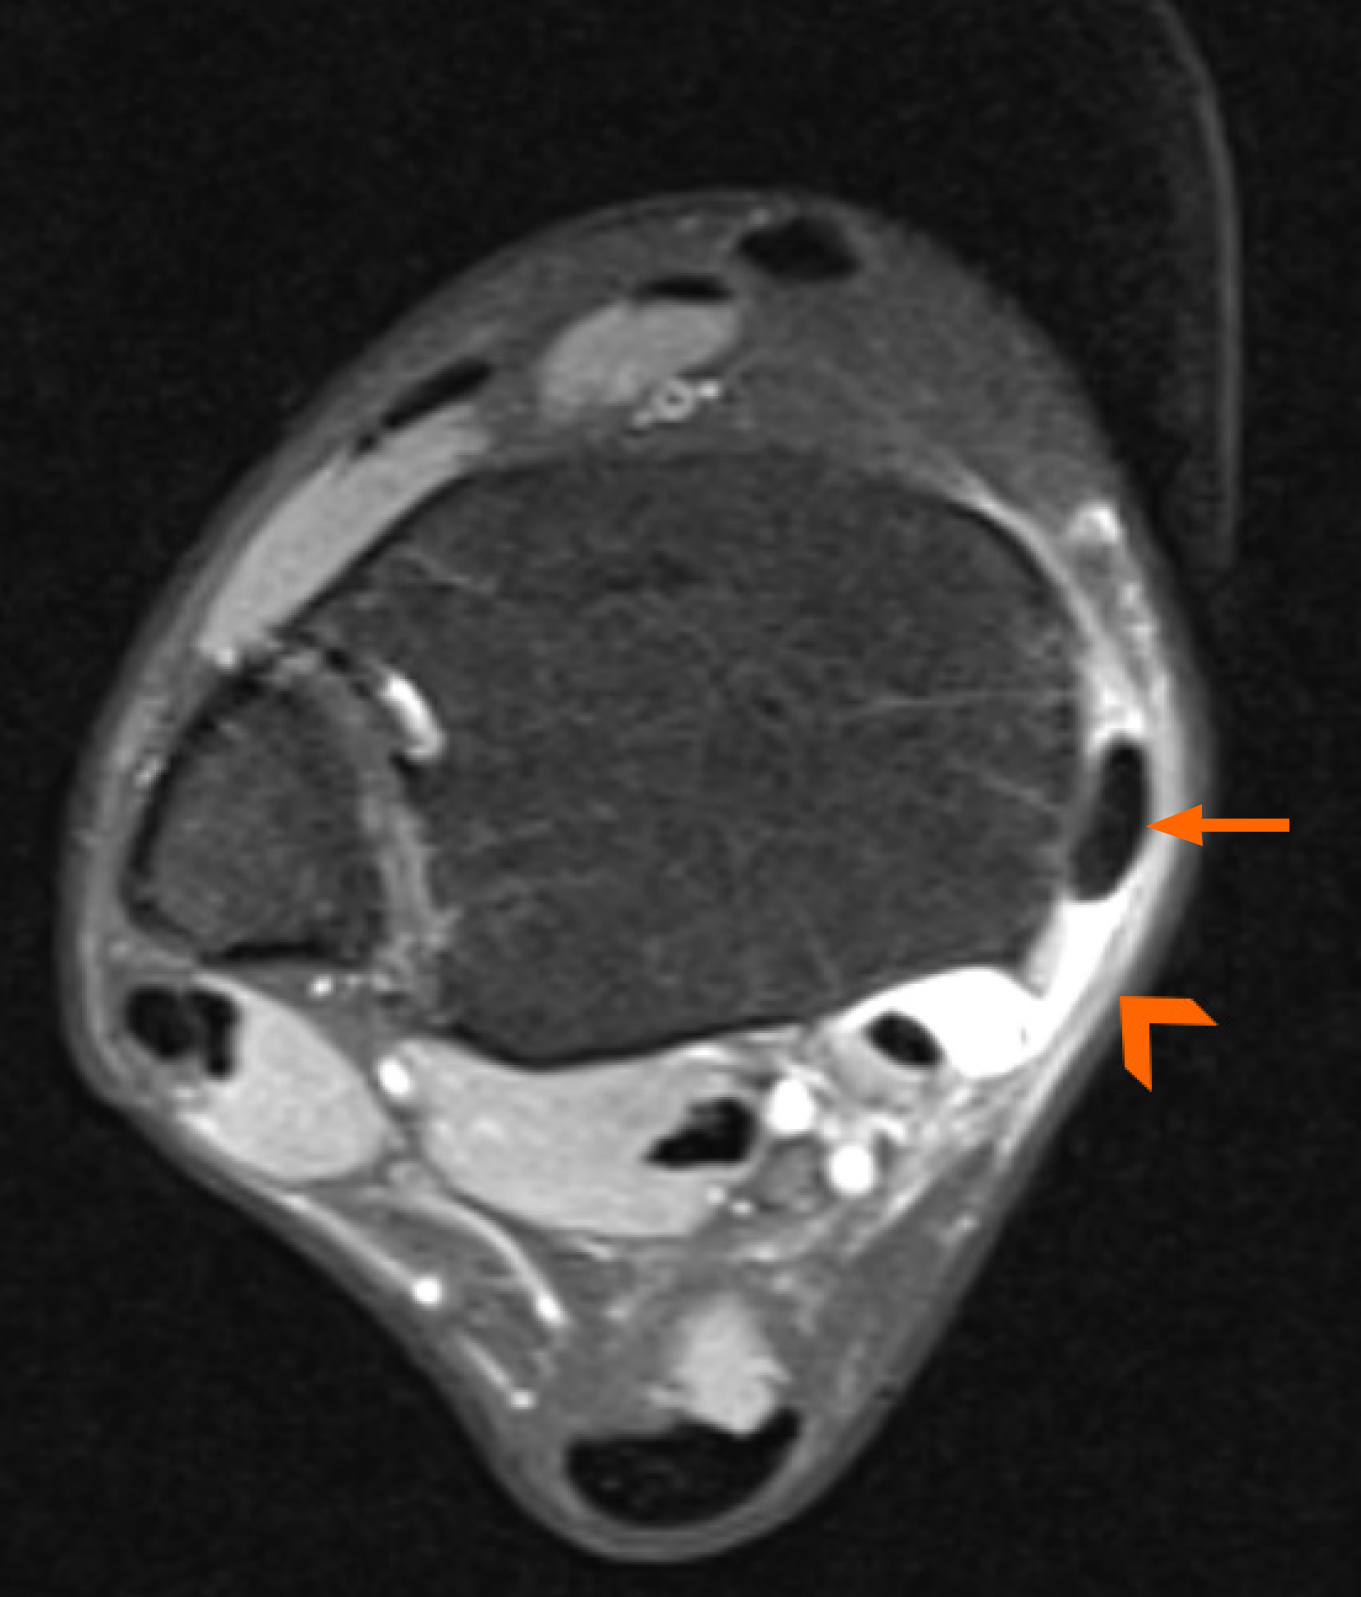

Figure 12 Magnetic resonance imaging of the dislocated posterior tibial tendon (arrow) underneath the redundant flexor retinaculum (arrowhead).